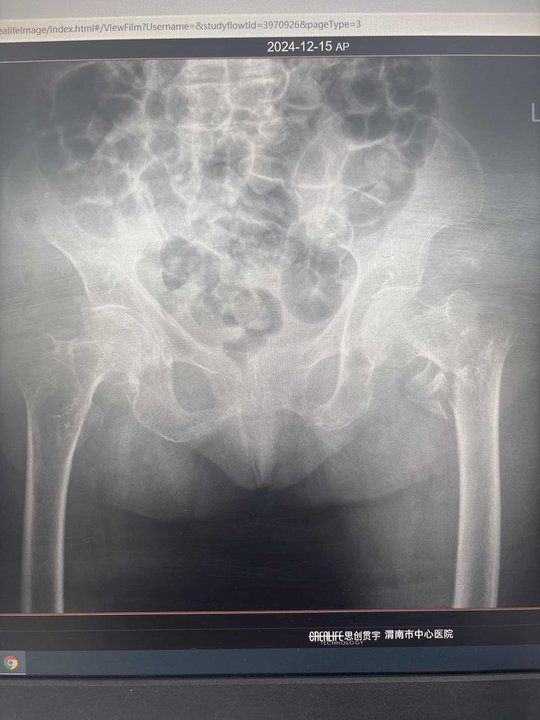

李某,女性,100岁,摔倒致左髋部肿痛伴活动障碍8小时,被送往市中心医院进行救治。患者行左髋X线示左股骨转子间骨折,收住入院。

手术前